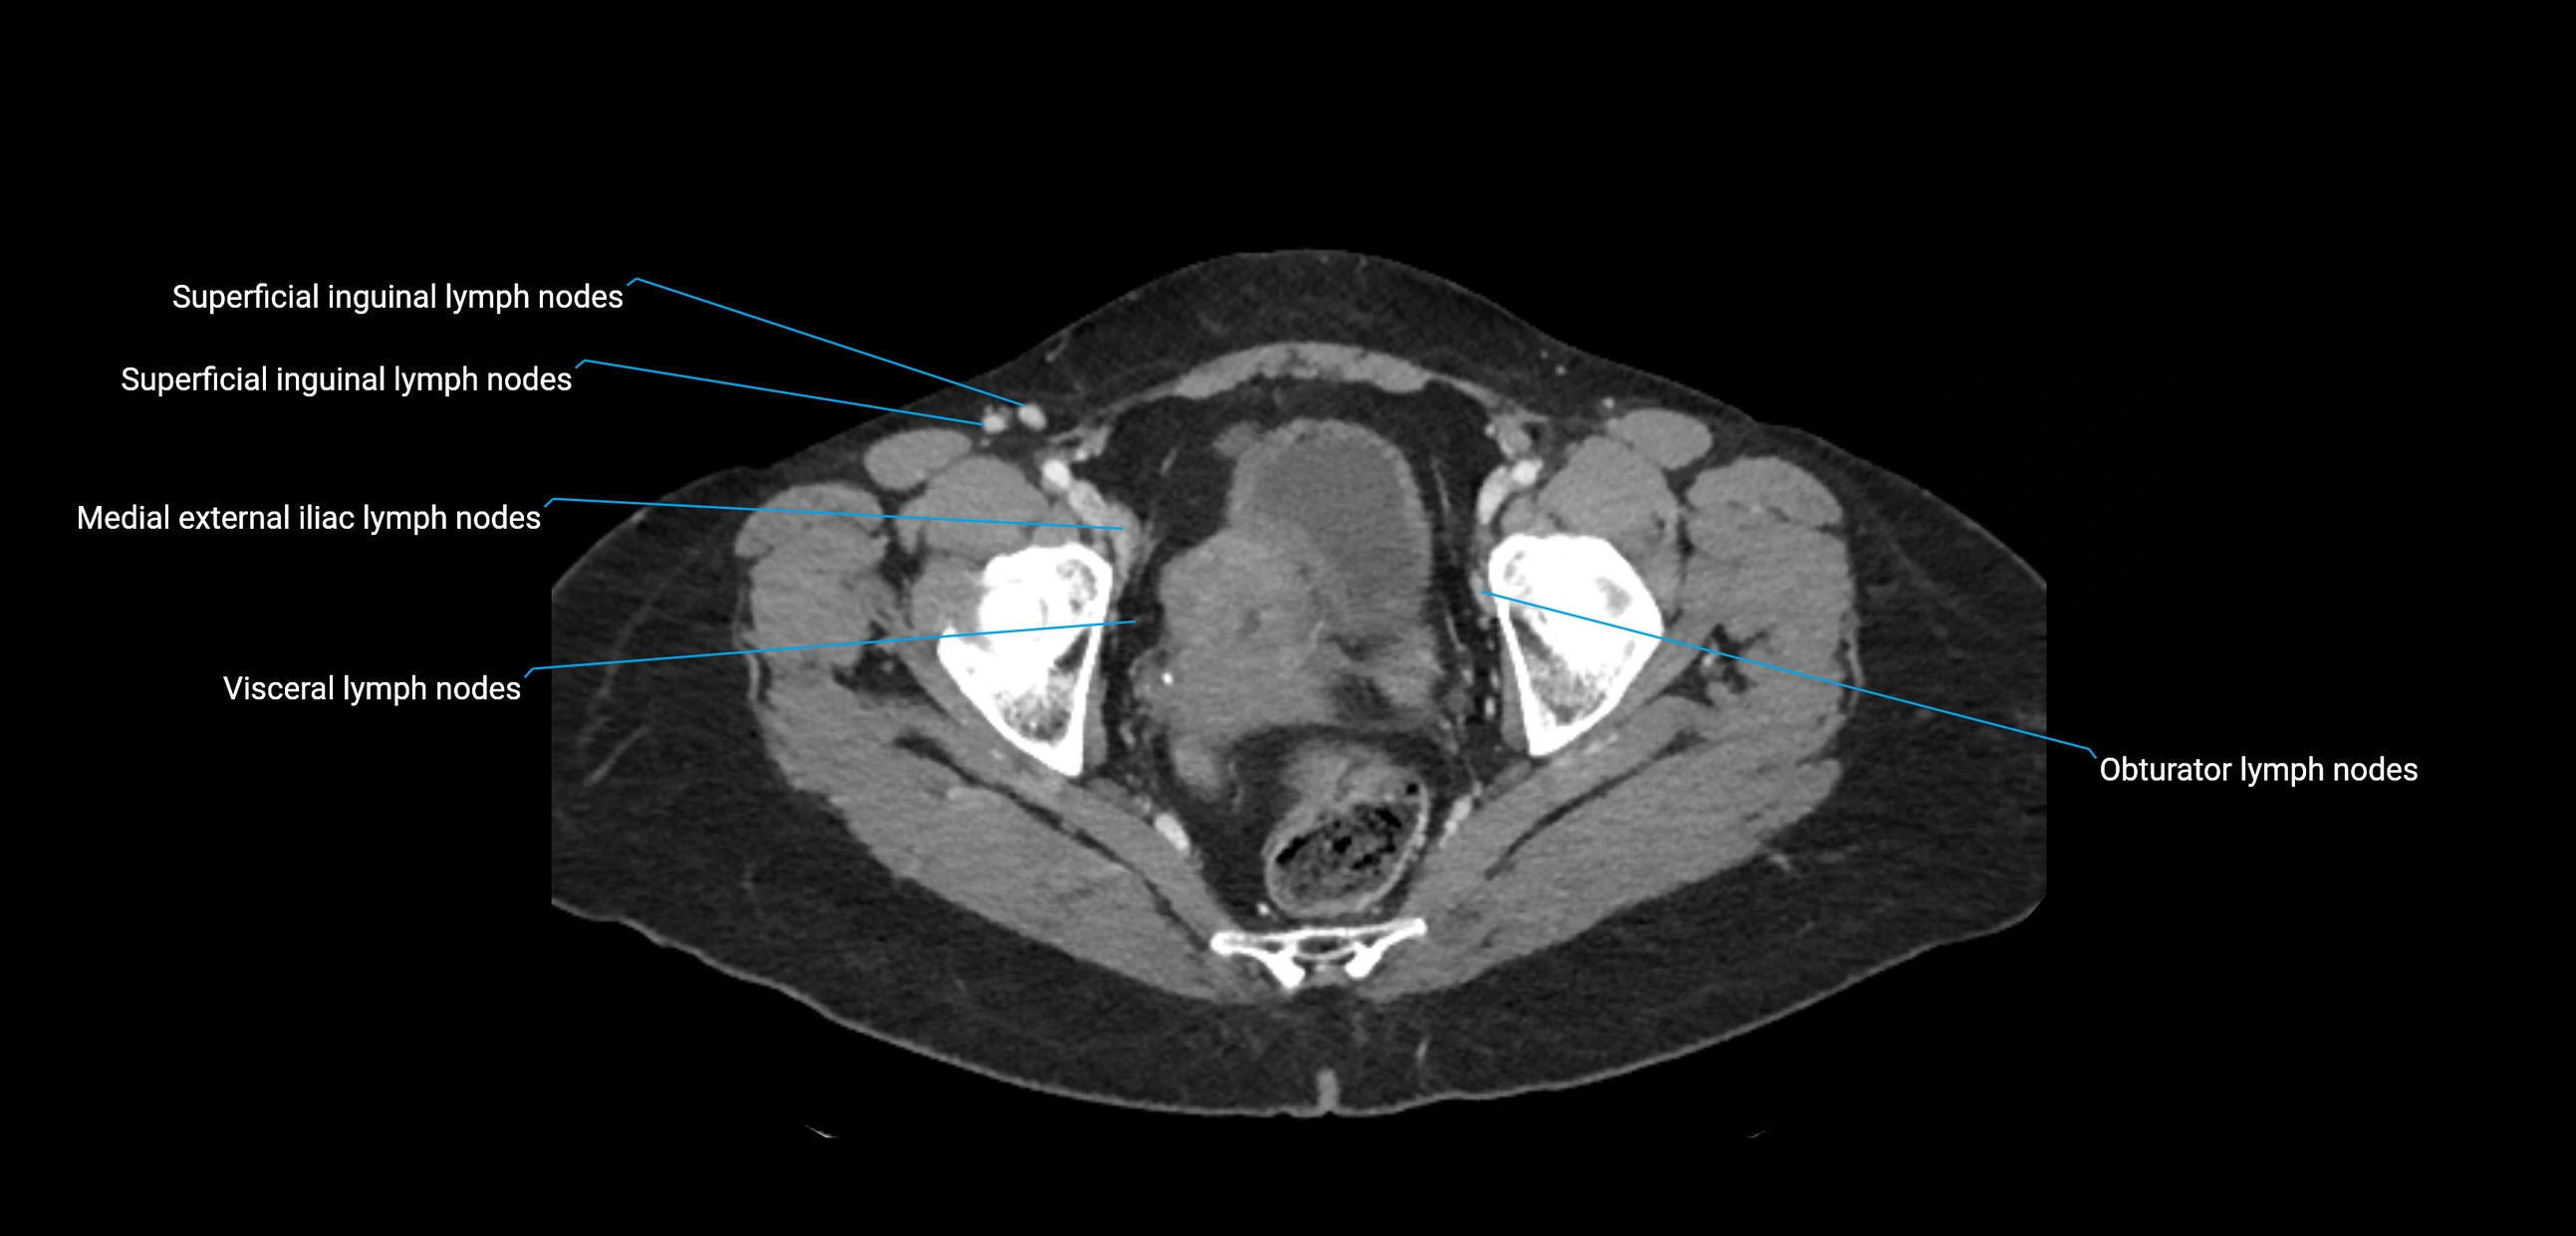

CT Appearance

CT Post-Contrast:

• Normal nodes enhance homogeneously

• Malignant nodes may show heterogeneous enhancement, central necrosis, or conglomerate formation

• Size >1 cm short axis is suspicious, though morphology and distribution are equally important

CT Venography (CTV):

• Demonstrates nodal encasement or compression of adjacent vessels (aorta, IVC, renal veins)

• Useful in staging testicular and ovarian malignancies

• Provides 3D reconstructions for retroperitoneal lymph node dissection planning